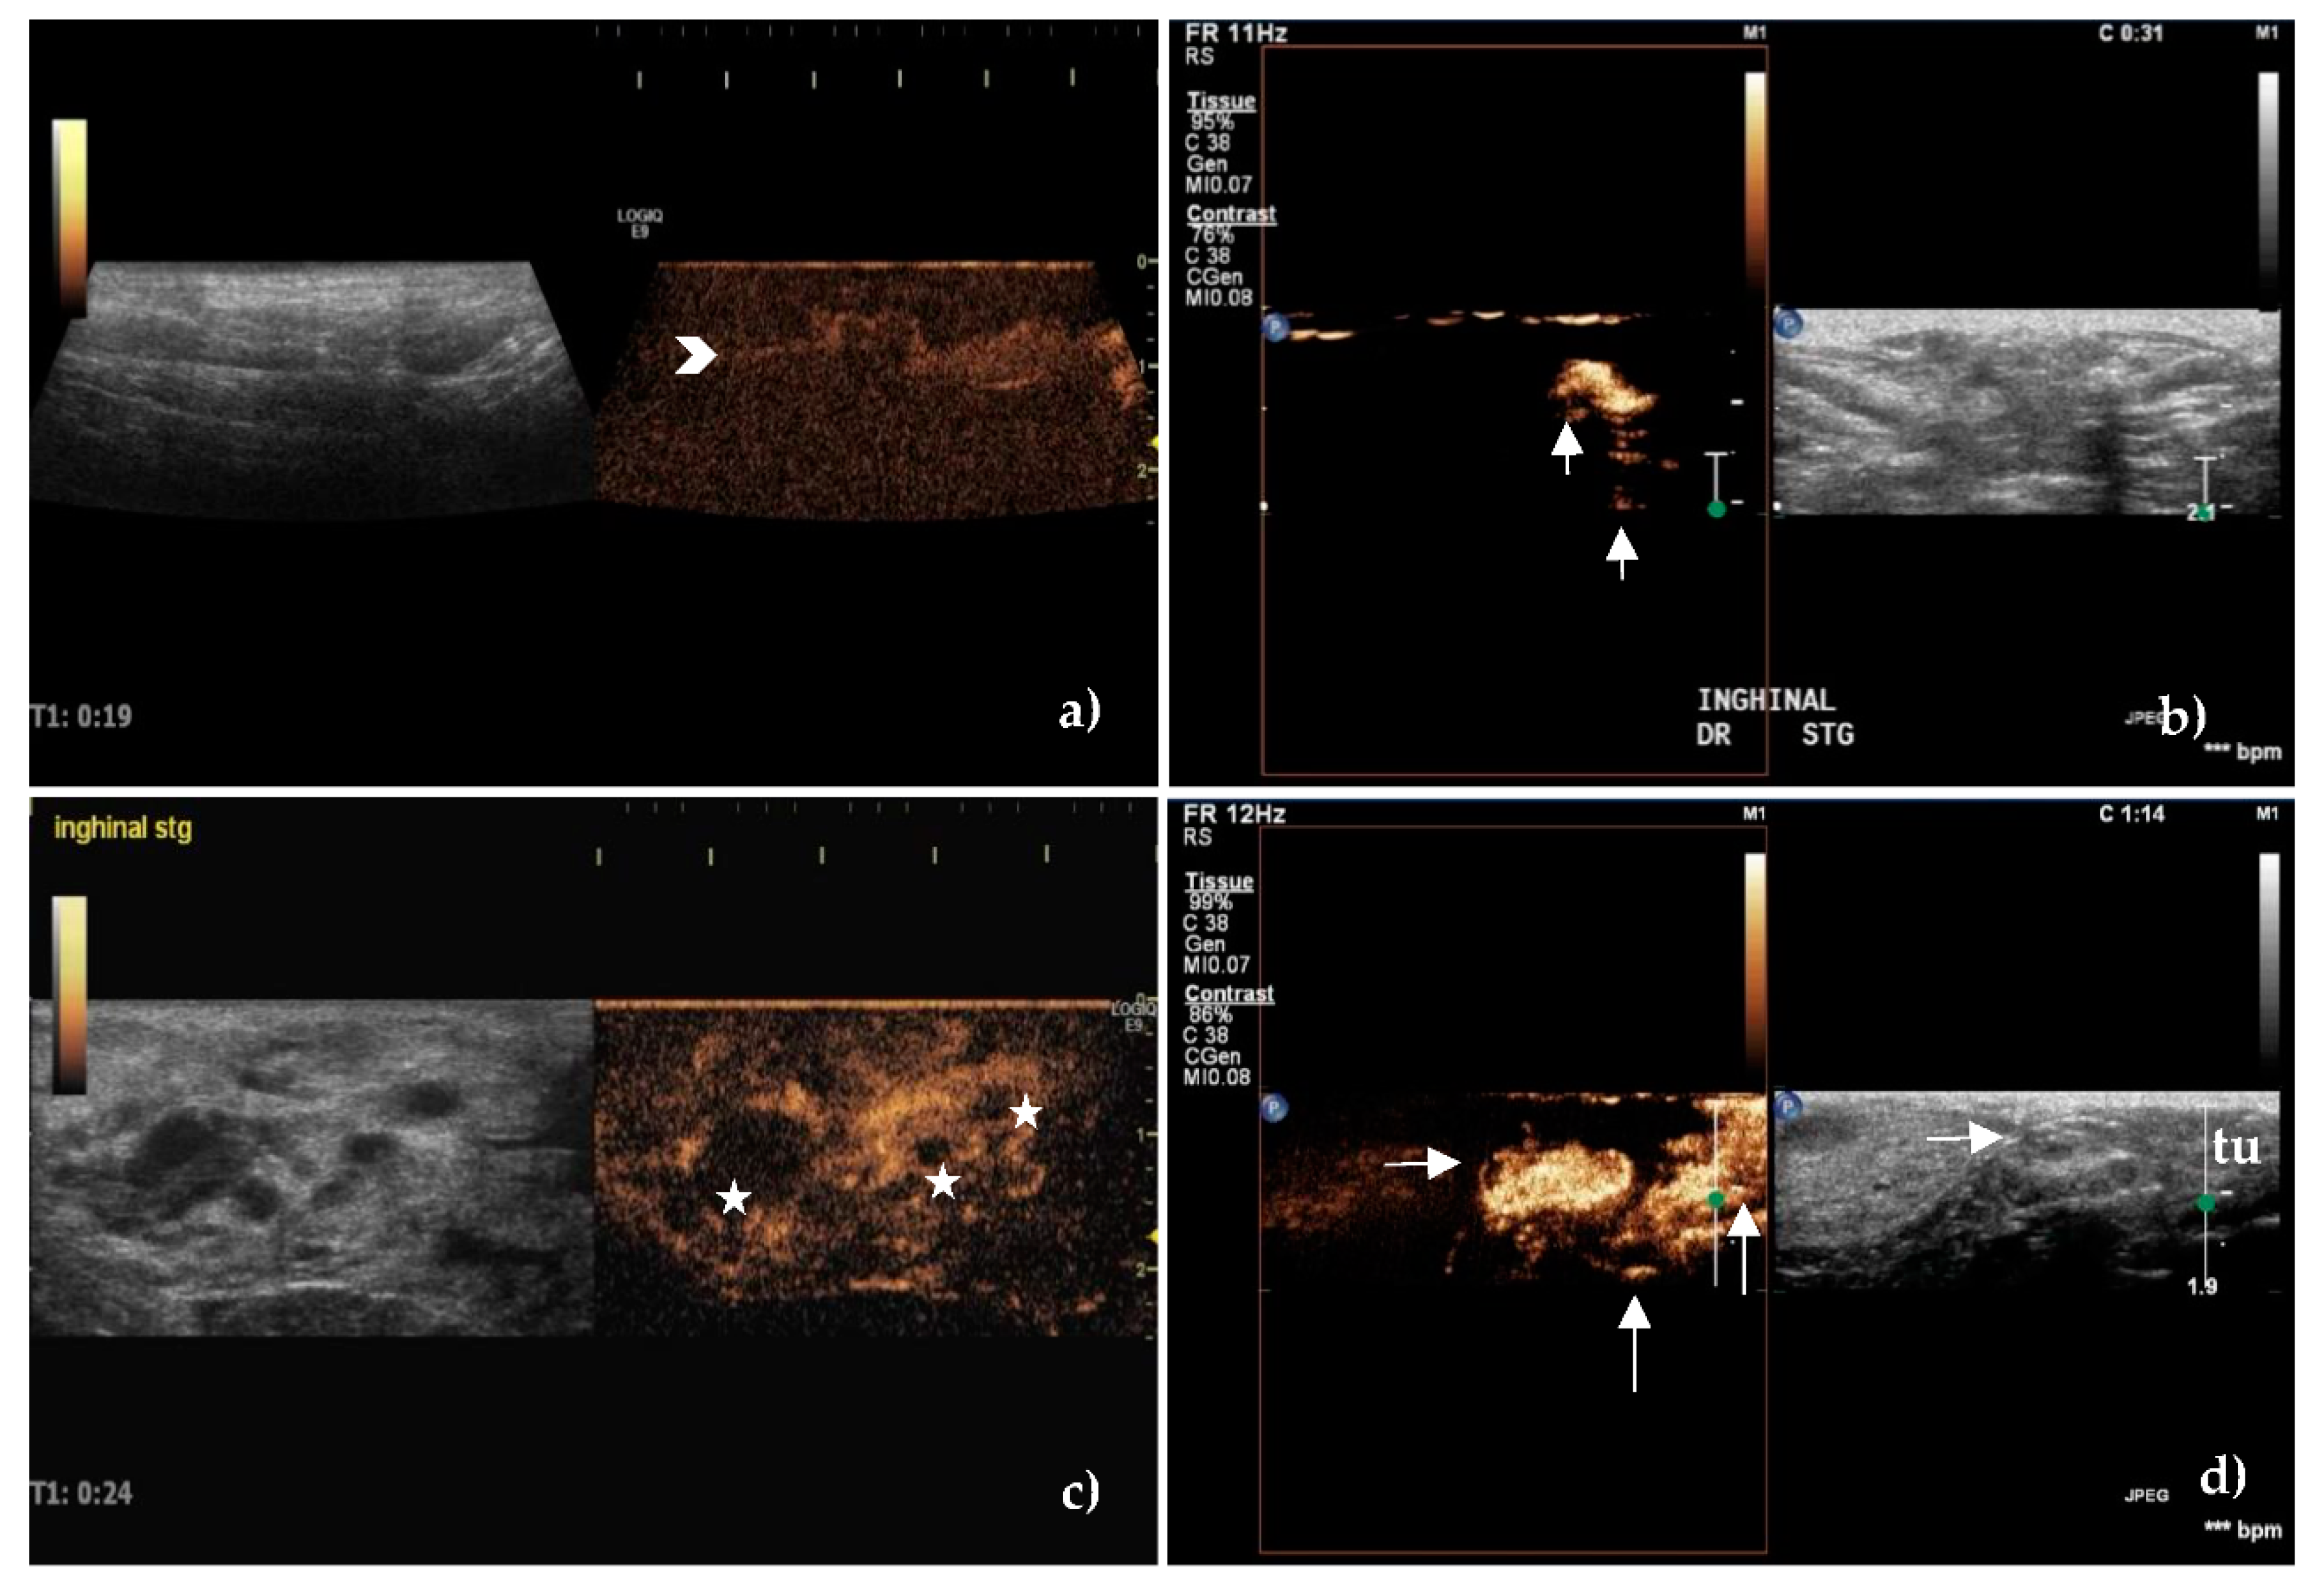

3.3. Contrast-Enhanced Ultrasonography

| CONTRAST-ENHANCED ULTRASONOGRAPHY (CEUS) | |||

| Enhancement patterns | |||

| Intense homogeneouss | 32(76.19) | 6(11.11) | <0.001 |

| Inhomogeneous | 8(19.04) | 44(81.48) | |

| No enhancement | 2(4.76) | 4(7.40) | |

| Perfusion times (expressed by mean ± SD) | |||

| Wash in time/s | 18.12 ± 7.15 | 15.34 ± 7.23 | =0.07 |

| Wash out time/s | 151.48 ± 34.62 | 104.26 ± 39.67 | <0.001 |